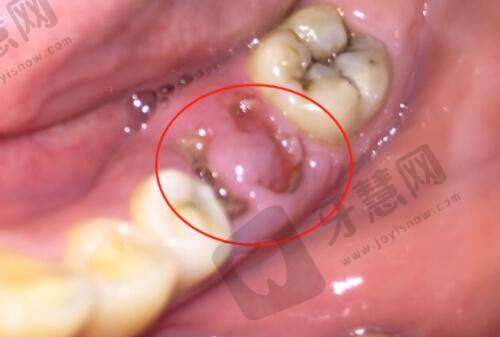

实例1:小王,29岁,小阴唇增厚术后3年

“刚做完:小阴唇对称又饱满,穿紧身裤再也不磨了,开心到飞起!

3年后:比刚做完时薄了约10%,但比没做前还是厚特别多,医生说正常,建议我做个激光巩固下,我准备下个月去。后悔吗?不后悔!3年花1.8万,平均每年6000,换3年舒适和自信,值了!”